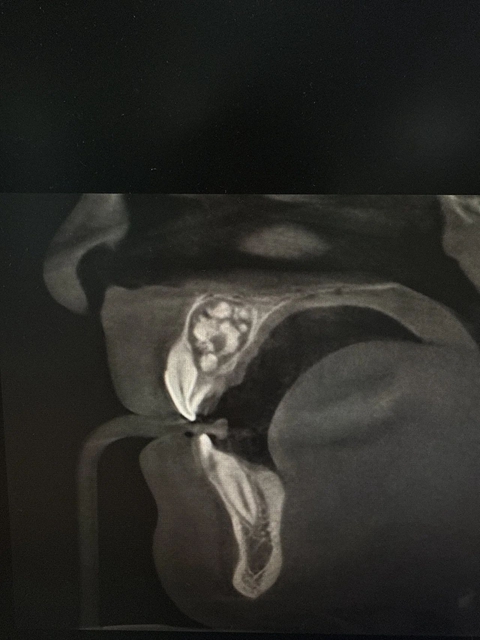

X线全景片:初筛显示颌骨内异常高密度影。

CBCT(锥形束CT):精确定位瘤体大小、位置及与邻牙、神经关系。组合性呈多个小牙,混合性呈钙化团块。

病理检查(确诊金标准):术后镜下见紊乱牙体组织。